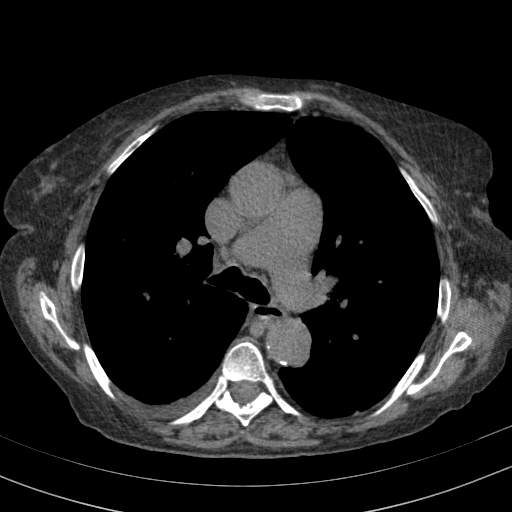

Original VENOUS CT scan

Full window (WL 1023.5, WW 4095 β†’ Low βˆ’1024, High +3071)

Actual HU range: [-1024.0, 1022.0]